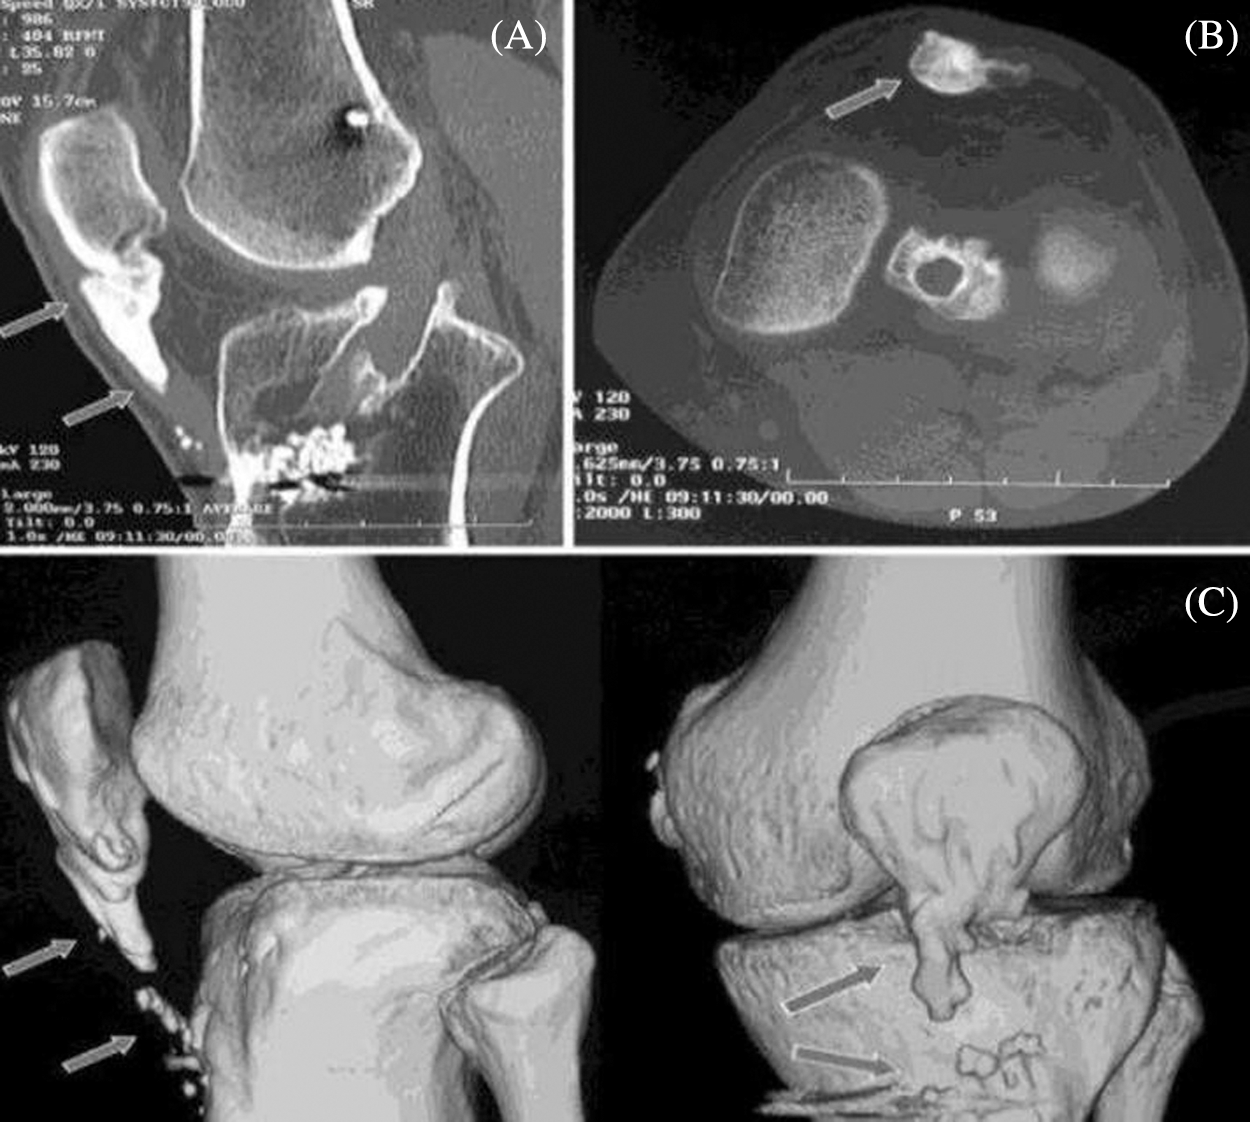

Osteoarthritis is a type of disease that mainly destruct the joint in knee, hip and hand and this disorder may happen when the cartilage cushion down the knee which starts to wear down [1]. Arthritis is joint inflammation which is characterized by joint stiffness which can lead to poor function. This mainly happens to age down and over weighted people. In osteoarthritis there are two main types which can be primary that happens to aged people and the secondary may occur to earlier stage due to injury in accidents, weak body conditions, and some diseases like diabetes. In our paper we are considering a CT image also termed as CT scans; to scan a knee image [2]. CT scan may show the cross-sectional images of knee so that the disorder can be defined clearly through image. The body is circled by a CT scanner and it transfers pictures to a computer. These pictures are used by the machine to create detailed images. This helps the joints, cartilage, ligaments, vessels, and bones that make up the knee to be seen by physicians and qualified technicians. CT images can be introduced with main advantages like quick access of image detection in knee, painless, availability is better compared with MRI scanning; the bones structures are visualized in good view [3]. CT scan may also view an image of a small portion of knee [4]. Fig. 1 shows the CT scan image of knee joint destruction.

Figure 1: CT scan image of knee joint destruction